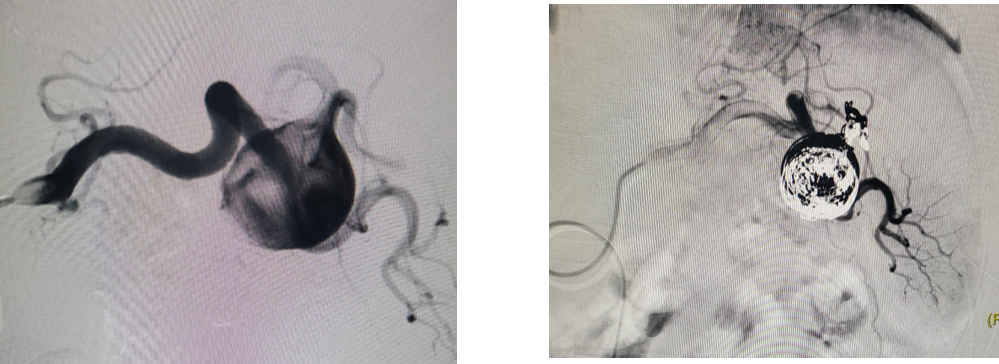

6

病例6 脾动脉瘤Viabahn支架隔绝

图为:术后复查

7

病例7 脾动脉瘤戴膜支架隔绝

8

病例8 脾动脉瘤破裂直接栓塞